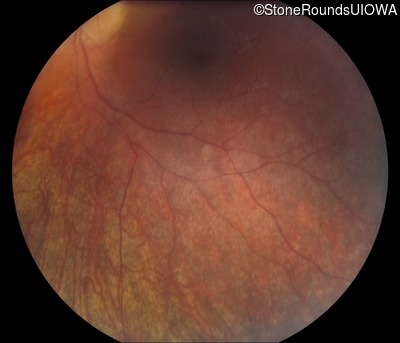

Fundus Photography - Right -

Light Perception

Exemplar

Expanded OCT Stack

×

Fundus Photography - Left -